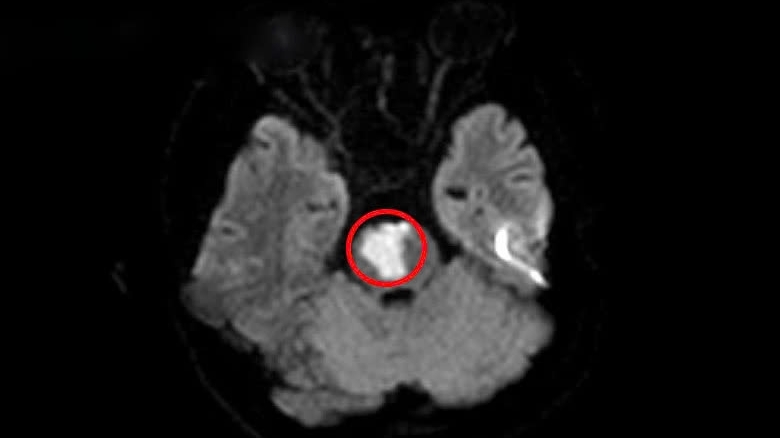

TS.BS. Nguyễn Trung Nguyên - Giám đốc Trung tâm Chống độc, Bệnh viện Bạch Mai cho biết, bệnh nhân nhập viện trong tình trạng hôn mê, suy thận, tổn thương cơ. Tình trạng hiện tại của bệnh nhân dù đã có ý thức nhưng vẫn có dấu hiệu tổn thương não, suy thận, tổn thương cơ.

TS.BS. Nguyễn Trung Nguyên cho biết: “Bệnh nhân có thể không tử vong, tuy nhiên nguy cơ rất cao có những biến chứng thần kinh lâu dài. Đặc biệt là các vấn đề về mất trí nhớ, rối loạn tâm thần…. Chúng tôi đang cố gắng sử dụng các biện pháp điều trị tích cực để hạn chế những biến chứng cho bệnh nhân trong thời gian tới”.

Bên cạnh đó, bác sĩ cũng chia sẻ đó mới là giai đoạn đầu, còn giai đoạn sau cũng rất đáng ngại. Khi bệnh nhân bị ngộ độc nhưng không tử vong thì sau một vài tuần sẽ gặp hiện tượng não bị tổn thương, dẫn tới các biến chứng về tâm thần, thần kinh (mất trí nhớ, rối loạn tâm thần, run,...).